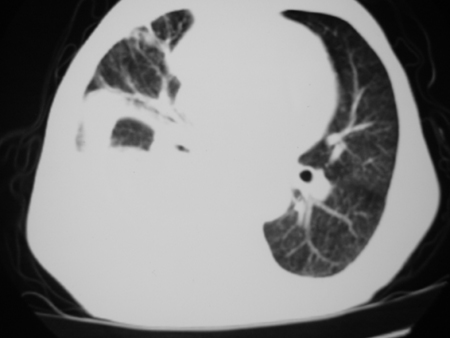

男77岁,胸痛就诊

考虑右肺门占位并下叶不张 右胸包裹积液

右侧胸腔积液,部分包裹,右下肺膨胀不全

右侧胸腔积液,部分包裹,右下肺膨胀不全,右下肺感染